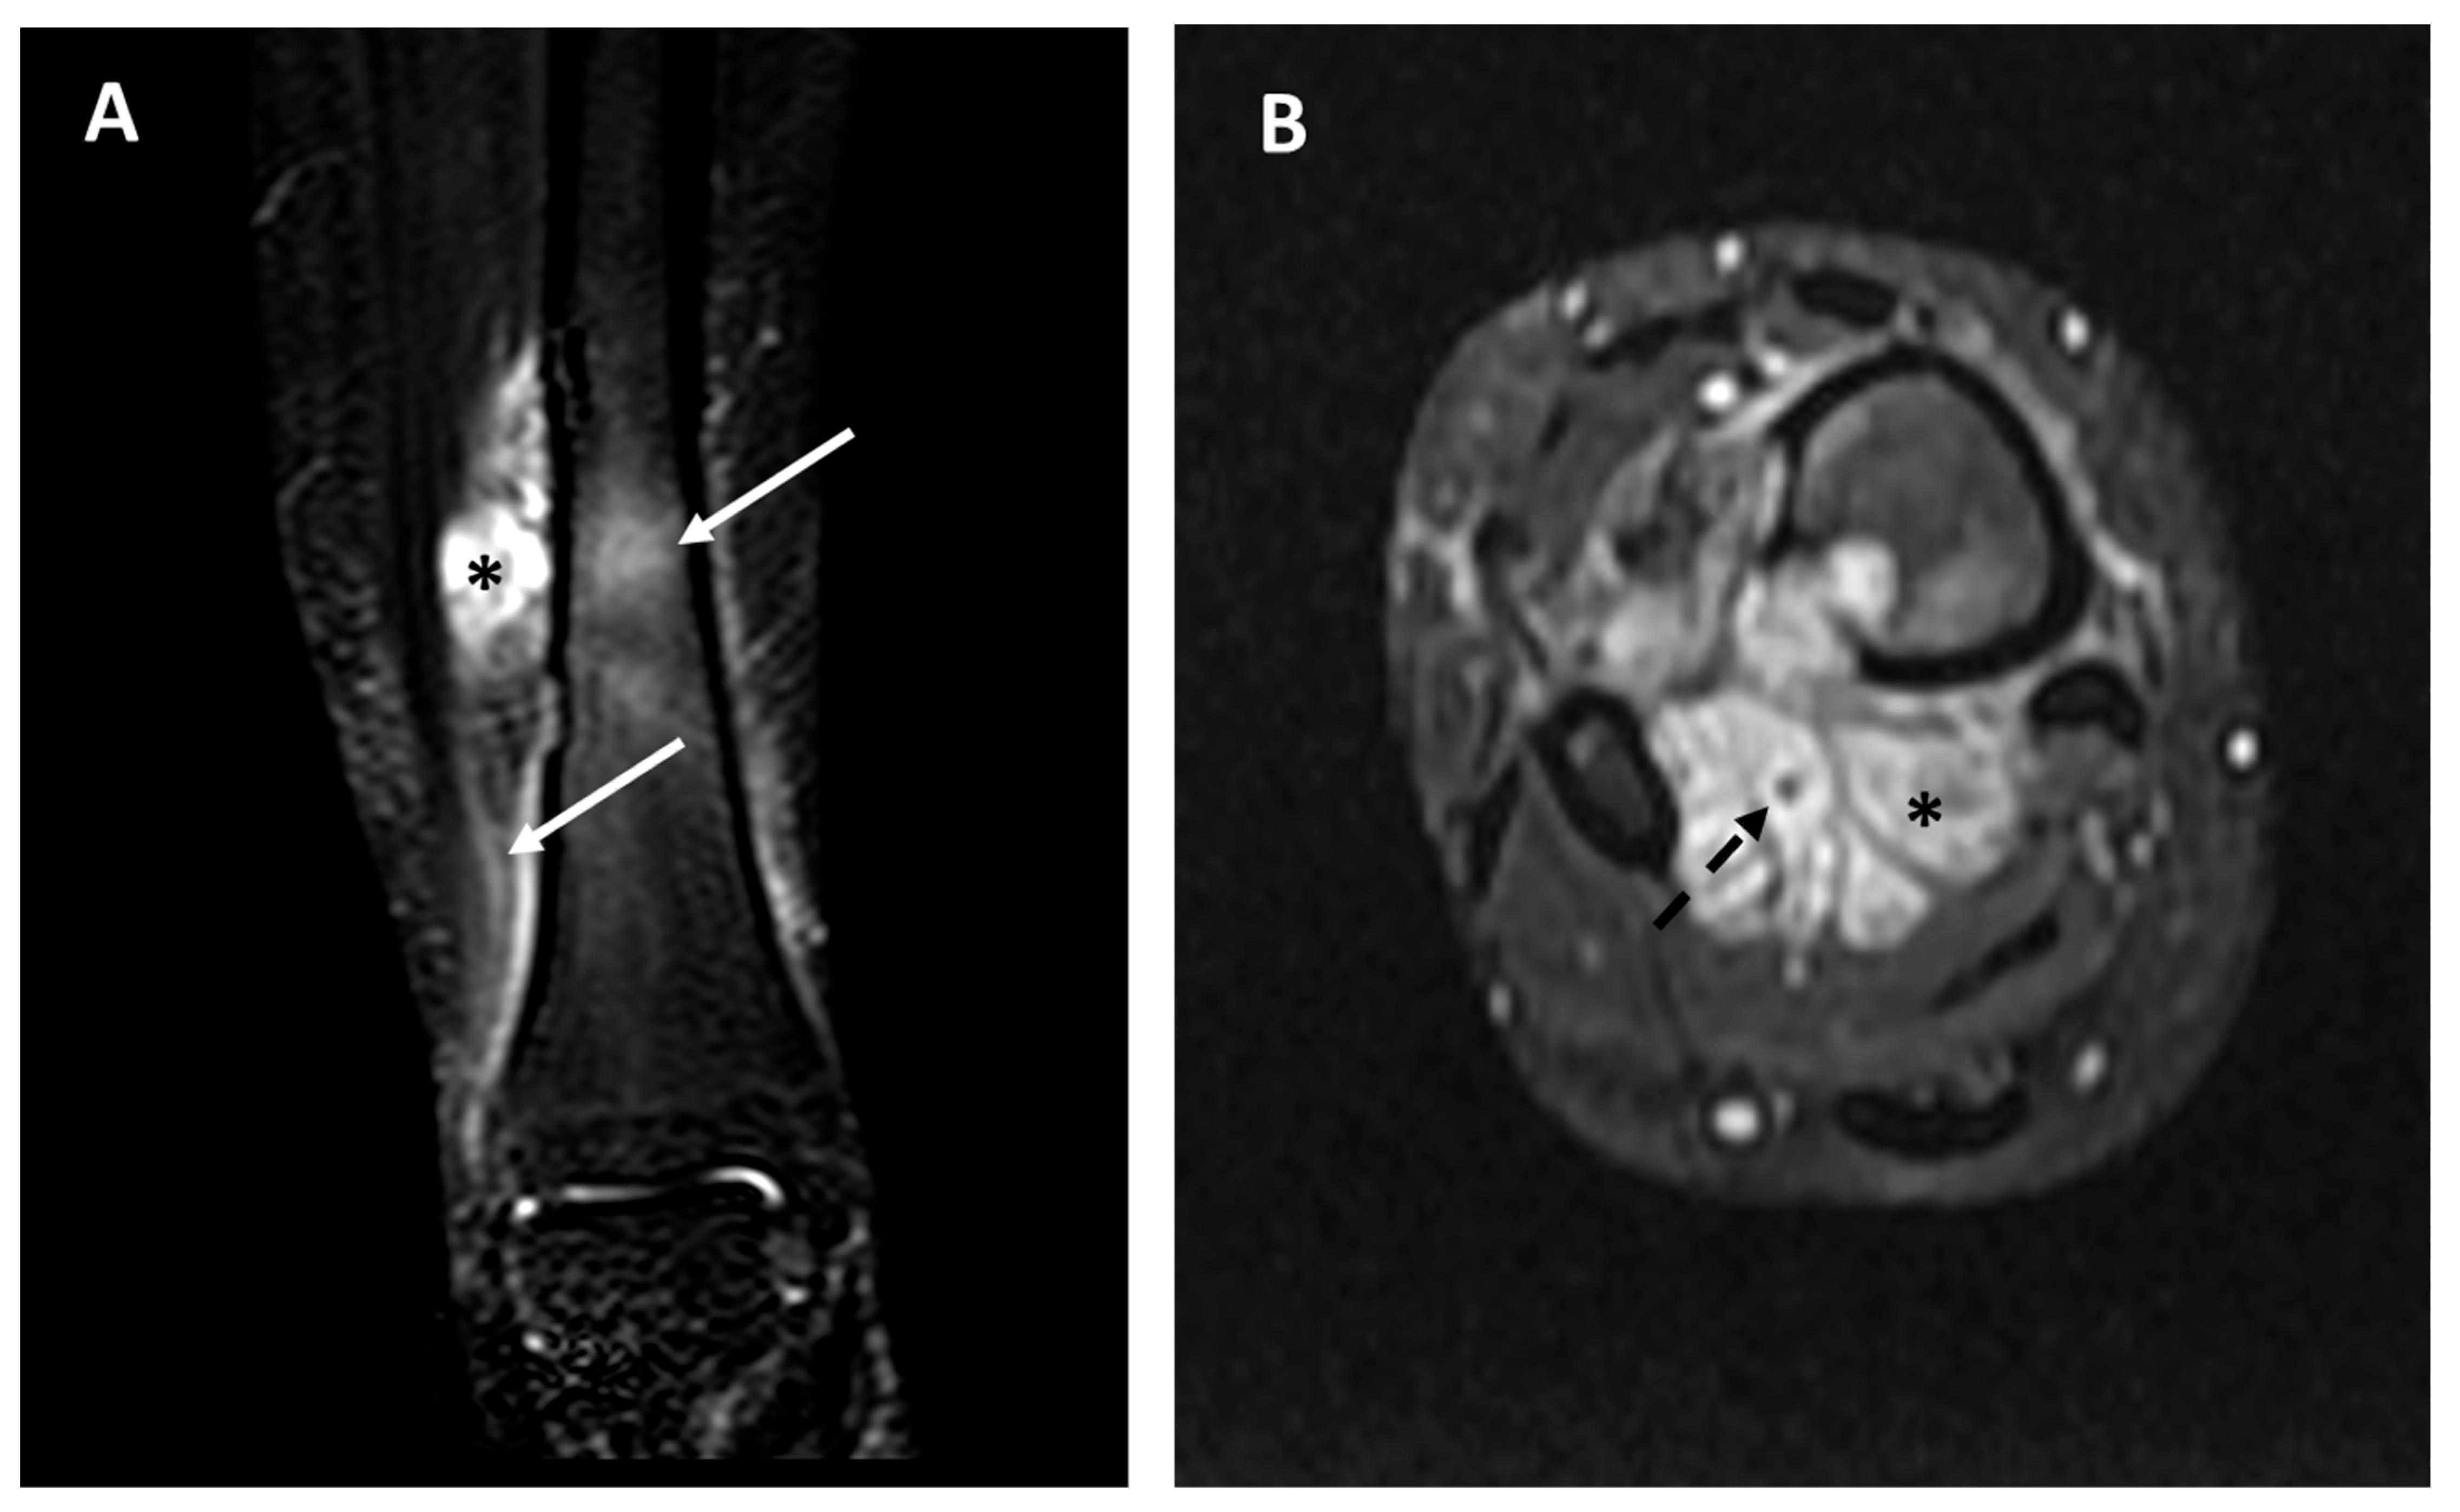

- Tumor extra-skeletal extension in the soft tissues (categorized as: absent, mild [i.e., smaller than the intra-osseous component], moderate [i.e., equal to the intra-osseous component], severe [i.e., larger than the intra-osseous component].

- Relationship/contact with the near major vascular bundles (categorized as absent, near <3 mm, in contact, and vascular encasement), as already performed in previous sarcoma studies [14].

- Internal necrosis (categorized as absent or present [i.e., macroscopic non-enhancing areas after contrast media intravenous injection]).

- Peritumoral edema (categorized as absent, focal [only intraosseous, or only extra-osseous], and diffuse [intra- and extra-osseous]).

- Peritumoral enhancement (categorized as absent, focal, or diffuse).

| Extra-intra osseus extension: Intraosseous only (0), intra- and extra-osseous (1) | Intraosseous only (14), Extra-osseous (2) | Intraosseous only (0), extra-osseous (6) | 0.0004 * |

| Vascular invasion: No vascular contact (0), Vascular contact or encasement (1) | No vascular invasion (16), Vascular invasion (0) | No vascular invasion (1), Vascular invasion (5) | 0.0002 * |

| Peritumoral edema: absent or focal (0), diffuse intra and extra-osseous (1) | Absent or focal (14), diffuse (2) | Absent or focal (0), diffuse (6) | 0.0004 * |

| Peritumoral enhancement: absent (0), present (1) | Absent (11), Present (1) | Absent (0), present (5) | 0.001 * |